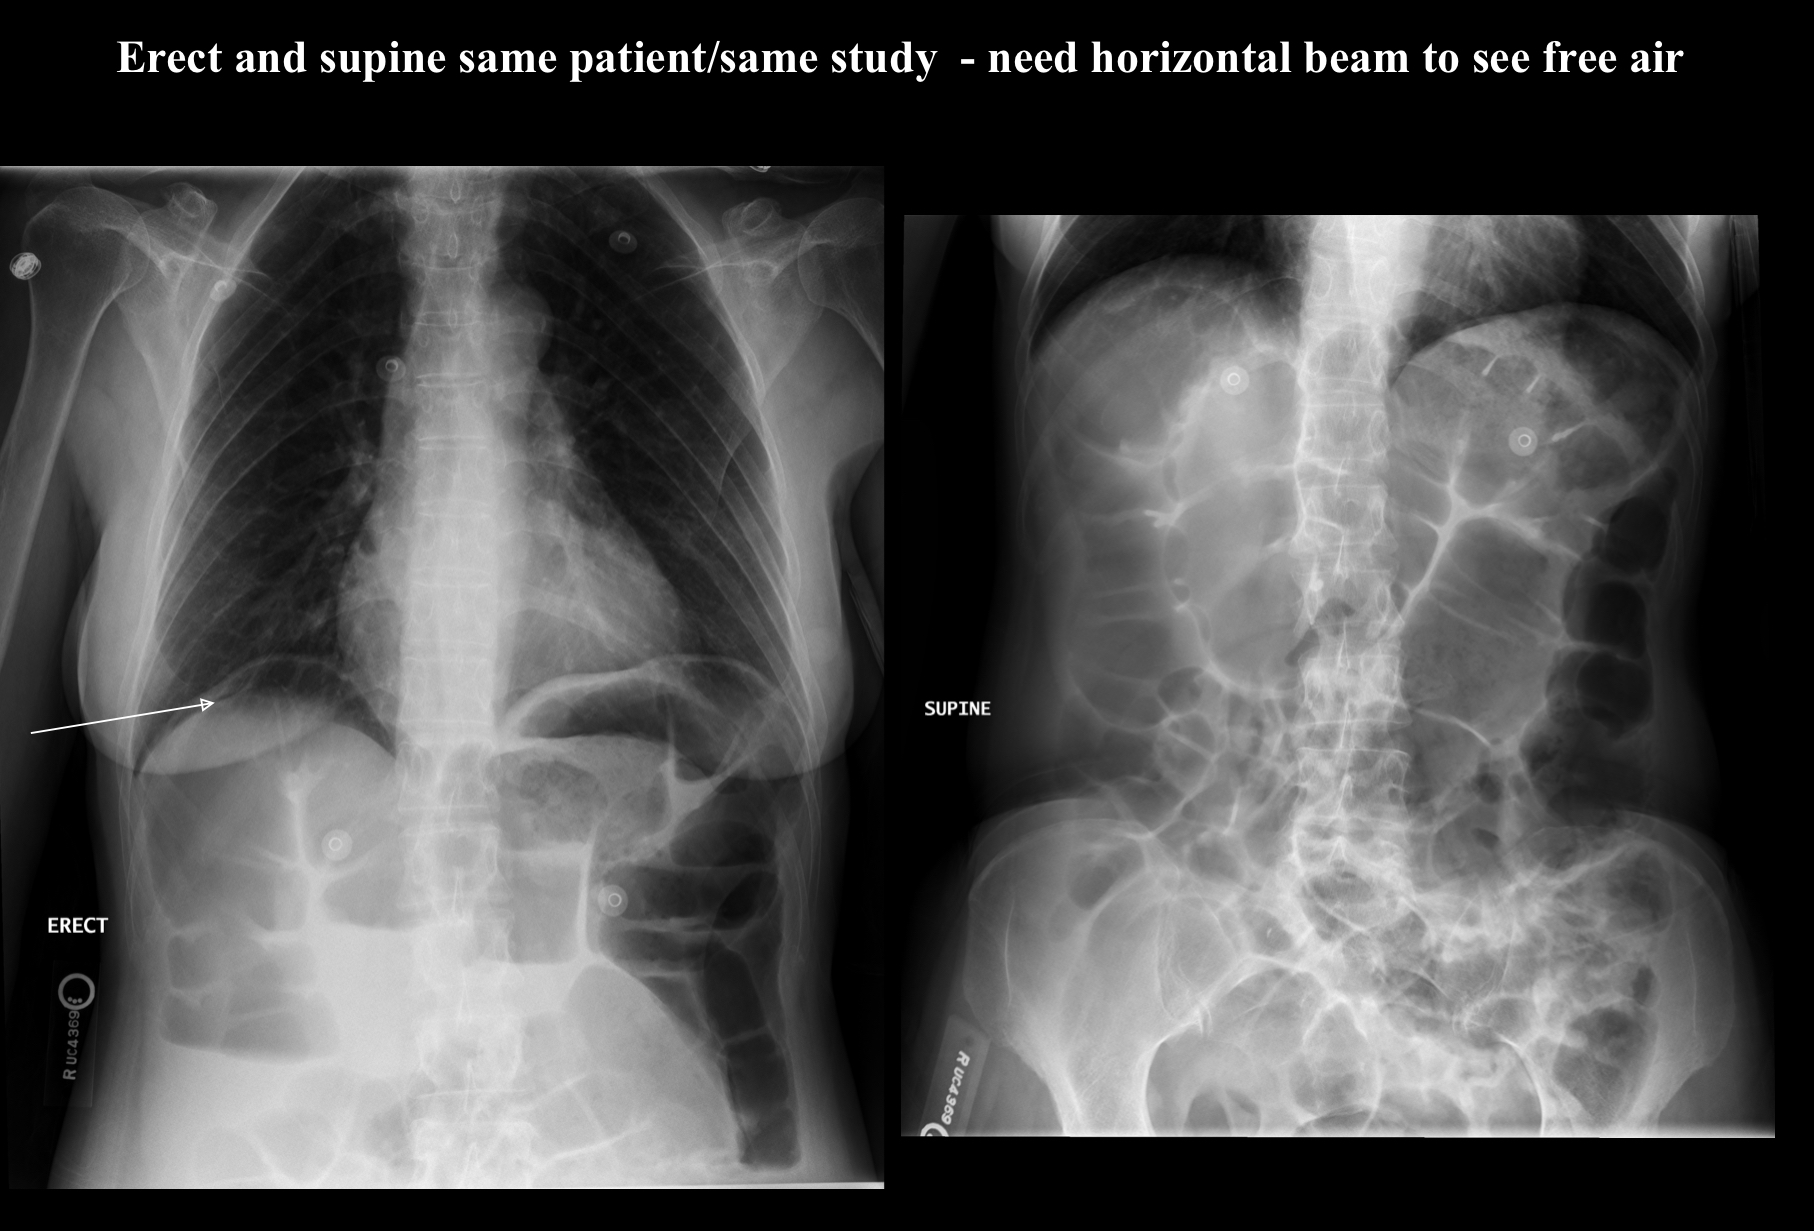

pneumoperitoneum

free air in the peritoneal cavity of abdomen

radiologic appearance of pneumoperitoneum

air accumulating at the highest point

technical factors of pneumoperitoneum

subtractive (decrease technique due to additional air)

pneumoperitoneum can be seen on what x-ray?

chest

What pathology is this?